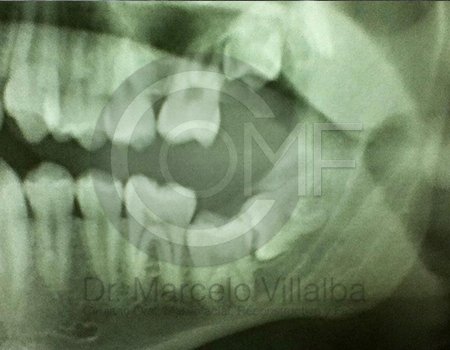

Antes de la extracción se realiza una valoración clínica y estudios de imagen, como radiografías panorámicas o tomografías, para conocer la posición del tercer molar, su relación con los nervios y planificar un procedimiento seguro y adecuado para cada paciente.

No es recomendable. Antes de extraer terceros molares es necesario realizar una valoración clínica y estudios de imagen para conocer la posición del diente, su relación con los nervios y el tipo de procedimiento más seguro para cada paciente.

Algunas extracciones simples de otras piezas dentales pueden ser realizadas por un odontólogo general; sin embargo, por la complejidad que presentan los terceros molares, o si se encuentran retenidos, impactados o cerca de estructuras importantes, se recomienda que el procedimiento sea realizado por un cirujano maxilofacial para mayor seguridad y control del tratamiento.